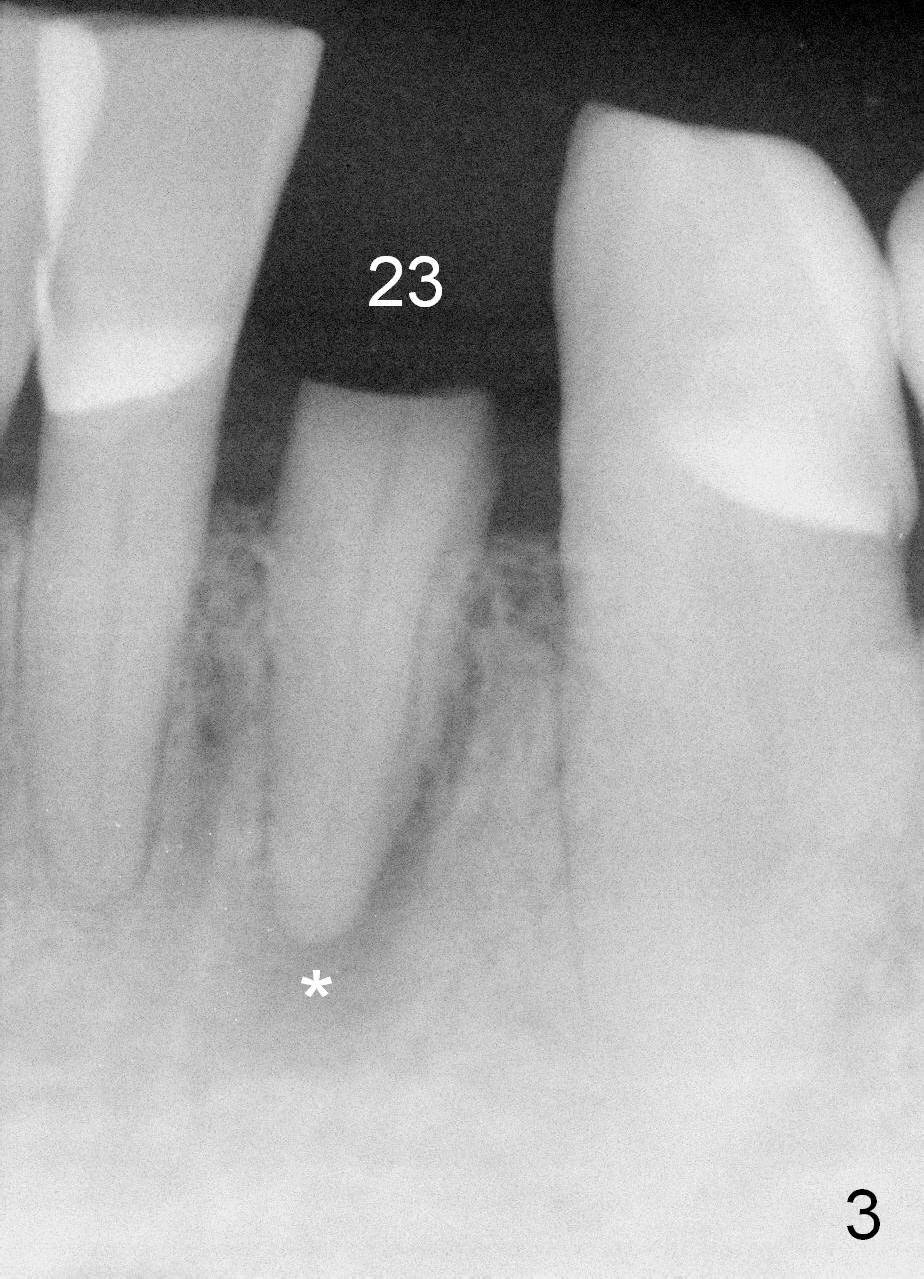

A 74-year-old man has several missing teeth (Fig.1). His 1st goal is to replace the lower left lateral incisor (Fig.2). The residual root has an apical lesion (Fig.3 *). To describe intraop findings, a CT image of a different patient is used (Fig.4 coronal section; B: buccal; L: lingual). After extraction, the buccal plate is found to be thin and low (Fig.5 arrowheads). A 1.5 mm pilot drill (Fig.6 red line) is used to initiate osteotomy in the lingual plate of the socket. Once the drill penetrates the lingual plate, the trajectory changes and the depth is 17 mm from the gingival margin (Fig.7). A PA is taken (Fig.8); it appears that the osteotomy can be extended more apically. When the pilot drill extends to 20 mm, there is sudden empty feeling. The lingual plate has perforated (Fig.9). A new osteotomy is established buccally (Fig.10 pink). To avoid buccal plate perforation, especially in the buccal undercut area (>), the coronal end of the drill has to be tilted buccally (<--). An angled abutment (3x20 mm, 15°) is placed (Fig.11,12). The abutment is modified (Fig.13,14) to accommodate an immediate provisional (Fig.15,16 P). Perio dressing is to be applied to prevent the bone graft from getting dislodged buccally (Fig.15). The dressing is in place 7 days postop (Fig.17).